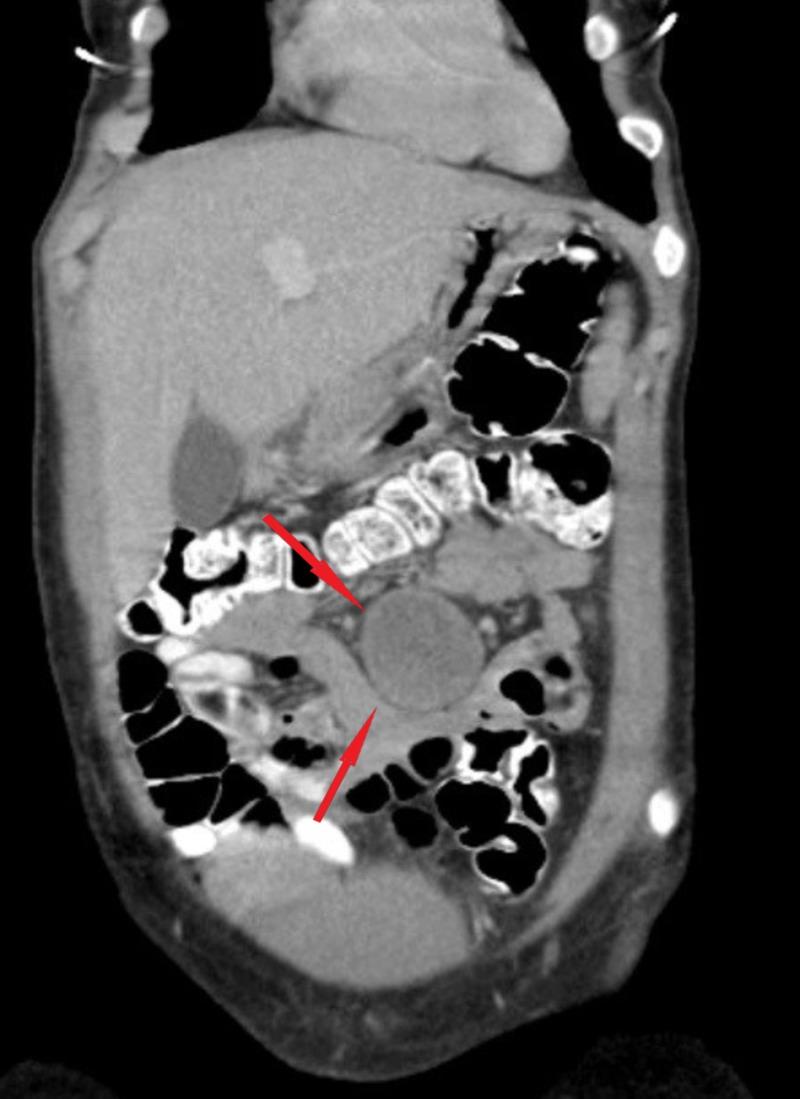

A rare case of a jejunal mesenteric pseudocyst treated by robotic resection is reported. A 25-year-old woman was admitted to our hospital with intermittent abdominal discomfort which was exacerbated by strenuous physical activities. Physical examination revealed a fluctuant mass without tenderness. Contrast-enhanced computed tomography revealed a 4 cm-sized non-enhancing heterogeneous mass on a proximal small bowel loop mesentery. Based on the findings, a differential diagnosis of a gastrointestinal stromal tumor, hematoma, desmoid tumor, and mesenteric cyst was made. Robotic diagnostic laparoscopy was performed to obtain an accurate diagnosis and treatment. Exploration of the cavity revealed a 4 cm fairly mobile mass originating from the mesentery of the jejunum. Segmental resection of the jejunum and its mesentery, including the mass and extracorporeal anastomosis, was performed without any complications. Macroscopically, the mass was cystic and the lumen had grumous material. The final pathological diagnosis was a mesenteric pseudocyst. The patient had an uneventful postoperative course.

报道了一例采用机器人切除术治疗空肠系膜假性囊肿的罕见病例。一名25岁女性因间歇性腹部不适入院,剧烈体育活动会使不适加剧。体格检查发现一个有波动感的肿块,无压痛。增强计算机断层扫描显示在近端小肠袢系膜上有一个4厘米大小的无强化的不均匀肿块。根据这些发现,对胃肠道间质瘤、血肿、硬纤维瘤和肠系膜囊肿进行了鉴别诊断。进行了机器人诊断性腹腔镜检查以获得准确的诊断和治疗。探查腹腔发现一个4厘米大小、相当活动的肿块,起源于空肠系膜。对空肠及其系膜进行了节段性切除,包括肿块和体外吻合,未出现任何并发症。肉眼可见,肿块为囊性,腔内有凝块状物质。最终病理诊断为肠系膜假性囊肿。患者术后恢复顺利。